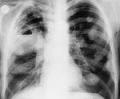

Фото: обзорная рентгенограмма органов грудной клетки больного эхинококкозом. В верхней доле левого легкого округлая тень с просветлением в центре. Рентгенологическая картина очень схожа с картиной инфильтративного туберкулеза легких с деструкцией легочной ткани (каверной). Без дополнительных исследований не разобраться. Часто эхинококк обнаруживают во время операции по поводу туберкулеза легких.